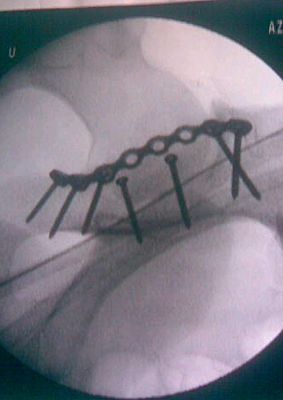

Dopo l’infortunio di Mercoledi scorso sul tracciato di Eersel, in Belgio, le condizioni di Marc De Reuver si stanno stabilizzando con il passar del tempo. Ieri pomeriggio l’equipe diretta dal Dott. Claes, ha operato all’anca sinistra il pilota olandese mentre in mattinata era gia stata effettuata la scansione alla schiena che aveva evidenziato alcune lesioni alle vertebre lombari. Dopo un consulto con lo staff medico, il Dott Claes ha deciso di dare priorità all’intervento chirurgico all’anca ed a seguire effettuerà controlli più approfonditi sulla colonna vertebrale del pilota prima di decidere quali terapie adottare per stabilizzare le lesioni. L’intervento all’anca è riuscito alla perfezione e la frattura è stata ridotta con l’applicazione di sette viti. Fino a giovedì Marc rimarrà in osservazione per il decorso post operativo, in seguito, l’equipe medica inizierà i controlli più approfonditi alla colonna vertebrale. Al momento, non si conoscono nè i tempi di degenza all’ospedale nè tantomeno i tempi di recupero che Marc dovrà rispettare prima di poter riprendere gli allenamenti.